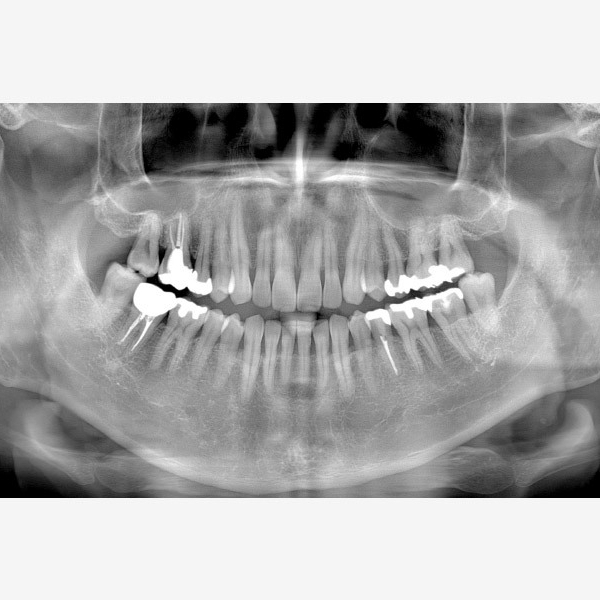

Information / DémonstrationPanoramique 3D & 2D

Veraview (X800) 2D/3D Panoramique +